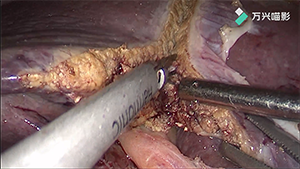

ICG荧光引导的腹腔镜下解剖性左半肝切除术

作者:王恺 | 作者单位:南昌大学第二附属医院